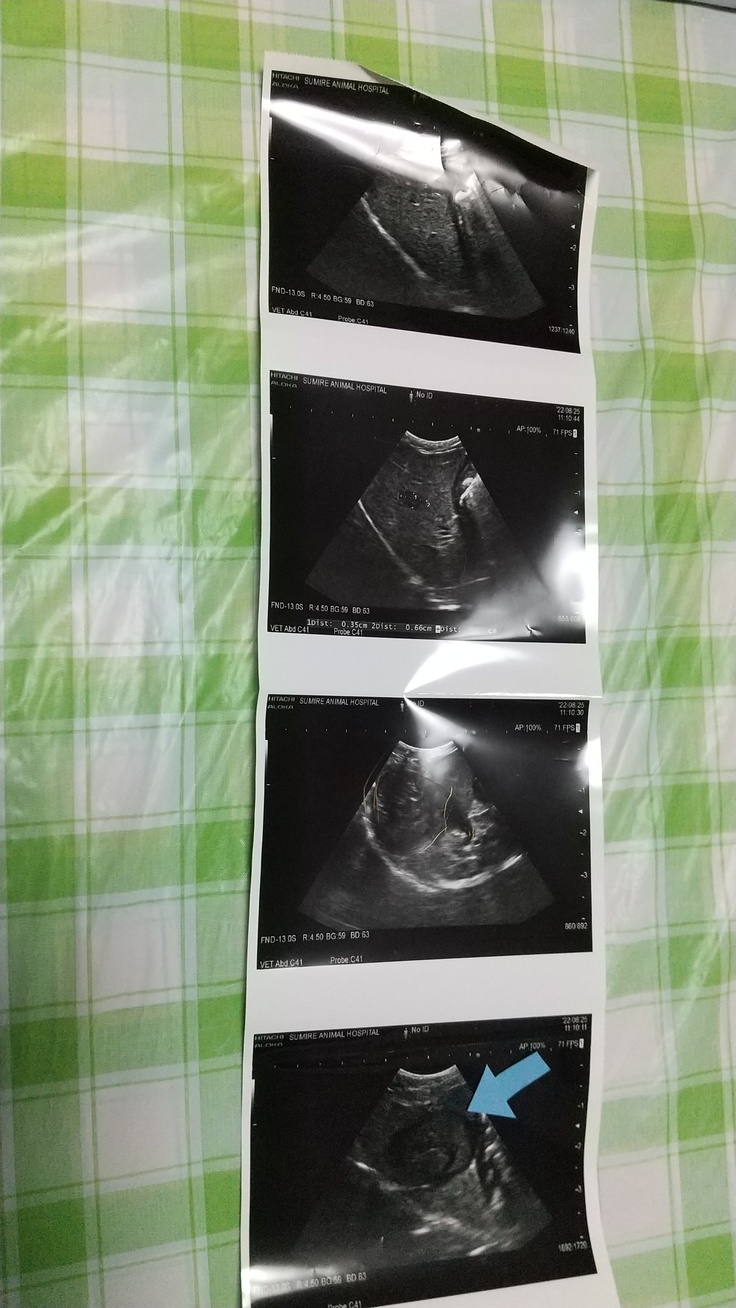

4日後に診察に行きました。少しは落ち着いたものの肝疾患と尿淡白の値が高いです、画像有り。8/29の画像。

今は処方された薬2種類飲ませております。

全て動物病院からの連載許可を得てます。